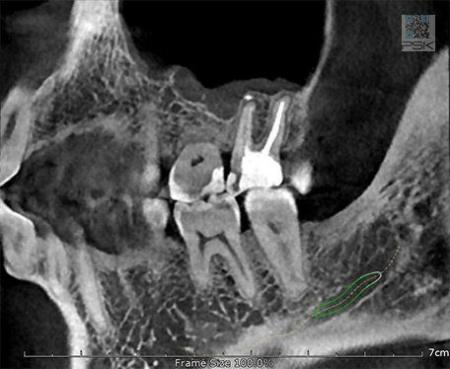

70 мкм в Эндодонтическом режиме 3,5×4 см

Высокотехнологичный детектор с самым высоким разрешением в классе – 70 мкм. Позволяет различить даже самые мелкие анатомические образования и облегчит постановку диагноза в сложных случаях. А вместе с применением алгоритма SMARF инородные тела из металла не испортят качество снимков.

Алгоритм уменьшения вторичного излучения от металлов

Умная Функция Уменьшения Артефактов от Металла (Smart Metal Artifact Reduction Function) – позволяет минимизировать артефакты от вторичного излучения металлов и получить необходимую диагностическую информацию для постановки корректного диагноза, а также планирования и контроля проведенного лечения.